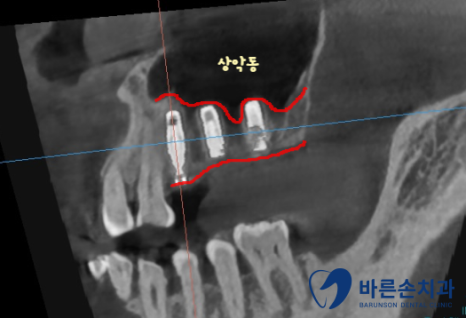

치료가 다 끝난 사진입니다!

임플란트도 뼈 안에 가지런히 잘 식립되어있습니다.

상실되어있던 치아들이 전부 생기게 되었고

치아색 보철로 내 치아처럼 자연스럽게 제작되었습니다

이제 아래 치아와 전부 맞닿게 되니까

식사 하시기 훨씬 편해지실겁니다!